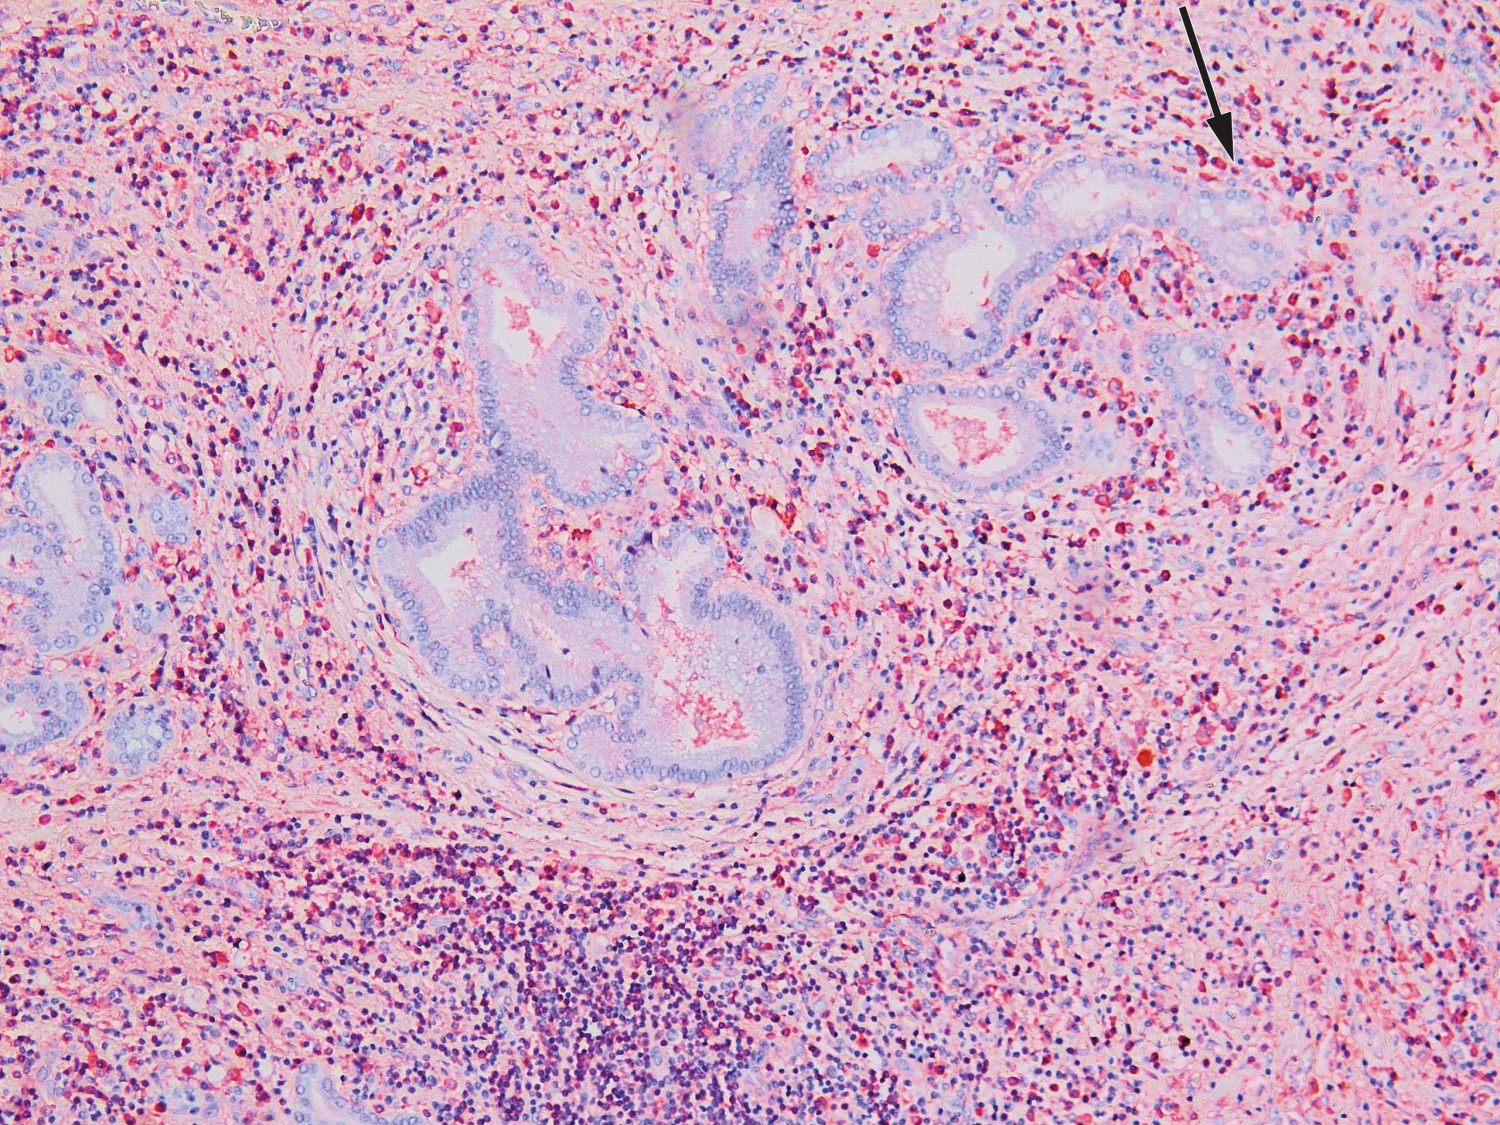

Seks dager etter overflytning ble det utført utvidet høyresidig leverreseksjon med hepatikojejunostomi. Postoperativt utviklet pasienten leversvikt med påfølgende iskemisk nekrose i gjenværende levervev. Tilstanden ble bedømt som meget alvorlig med liten sjanse for spontan bedring. Reseksjonspreparatet ble derfor undersøkt som cito-prøve i tilfelle tilstanden skulle være benign og dermed tillate transplantasjon. Histologisk prøve fra leverhilum viste ikke tegn til malignitet, men lymfoplasmacytære infiltrater og rikelig med eosinofile granulocytter. Immunhistokjemisk undersøkelse påviste overvekt av IgG4-positive plasmaceller og forhøyet IgG4/IgG-ratio på over 0,4 (figur 2). Serum-IgG4-prøve ble tatt postoperativt og var forhøyet på 6,0 g/l (0,03–2,01 g/l). Funnene var forenelige med IgG4-relatert sykdom.

Typiske funn i vevsbiopsi med lymfoplasmacytær betennelse, storiform fibrose og et forhold mellom IgG4- og IgG-positive plasmaceller på over 0,4 ved immunhistokjemisk undersøkelse regnes som gullstandard, men diagnosen må stilles ut ifra en kombinasjon av radiologiske, patologiske og serologiske funn (6). De mest kjente diagnostiske kriteriene er HISORt-kriteriene (histology, imaging, serology, other organ involvement og response to steroid therapy), som ble utarbeidet for diagnostikk av autoimmun pankreatitt og senere modifisert for IgG4-relatert skleroserende kolangitt (7).